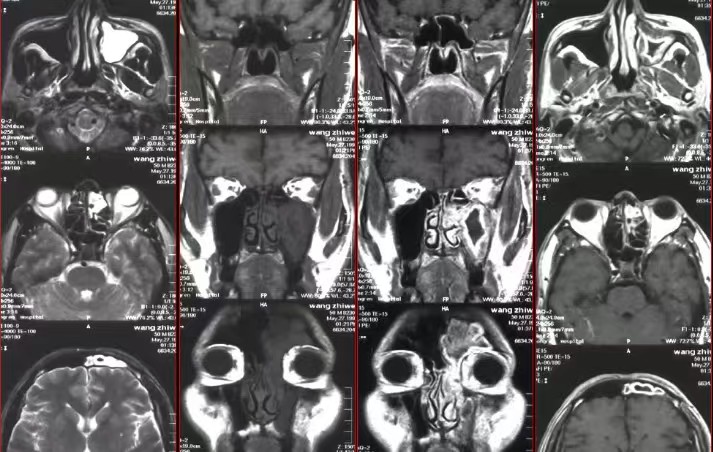

鼻窦解剖结构复杂,软组织交织分布。MRI对软组织分辨力强,能清晰区分黏膜炎性水肿、息肉样增生与正常组织,对早期病变及微小息肉的检出效果优于部分传统检查。在良恶性肿瘤鉴别中,可清晰显示肿瘤大小、形态及侵犯范围,为肿瘤分期和治疗方案制定提供关键依据。

3. 多方位成像,全面覆盖病变范围

MRI可实现轴位、冠状位、矢状位多平面成像,从多角度完整呈现鼻窦结构及病变,弥补单一视角局限,降低漏诊风险。对鼻窦深部隐匿炎症及向颅内、眼眶侵犯的病变,能清晰明确累及范围,提供全面诊断信息。